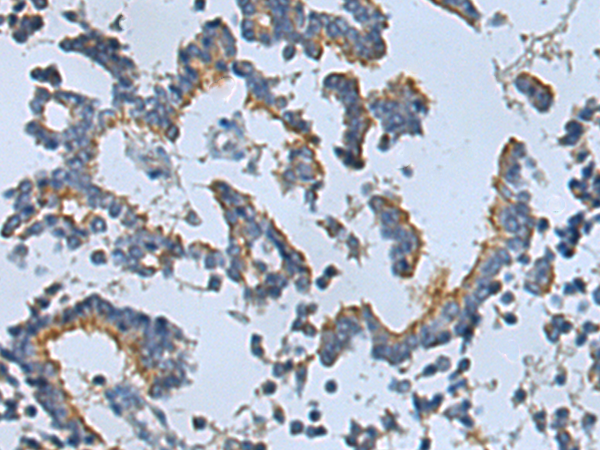

分类: 科研抗体货号: P05816别名: STMP; IPCA1; PUMPCn; STAMP1; PCANAP1应用: WB,IHC反应种属: Human, Mouse, Rat